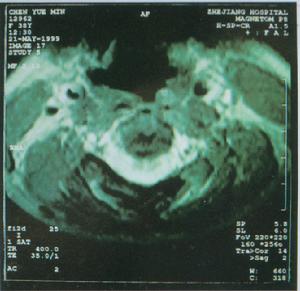

遺傳性痙攣性截癱HSP的診斷主要基於臨床症狀體徵,陽性家族史,並排除其他疾病。因此,HSP的鑑別診斷很重要,特別是對臨床特徵不典型及沒有相同疾病家族史的患者。目前,基因診斷已成為可能,但只限於已克隆的5型疾病基因的突變檢測。肌活檢有助於HSP-7型的診斷頸椎病常有上肢受累,神經根性疼痛,頸椎X線片及MRI示頸椎骨質增生。多發性硬化有緩解與復發的病史,視神經炎,MRI示腦部脫髓鞘改變。肌萎縮側索硬化有上肢肌萎縮,肌束震顫,肌電圖示巨大電位改變。Arnold-chiari畸形有共濟失調錶現,頭顱MRI可確診。脊髓小腦型共濟失調以共濟失調錶現為主,眼球運動障礙,構音障礙等。本病須與Arnold-Chiari畸形、頸椎病,多發性硬化、腦性癱瘓和遺傳運動神經元病等鑑別。

3、MRI頭顱MRI一般無異常,但某些病例可表現胼胝體發育不良,大腦、小腦萎縮。頸段或胸段脊髓MRI可顯示脊髓萎縮。